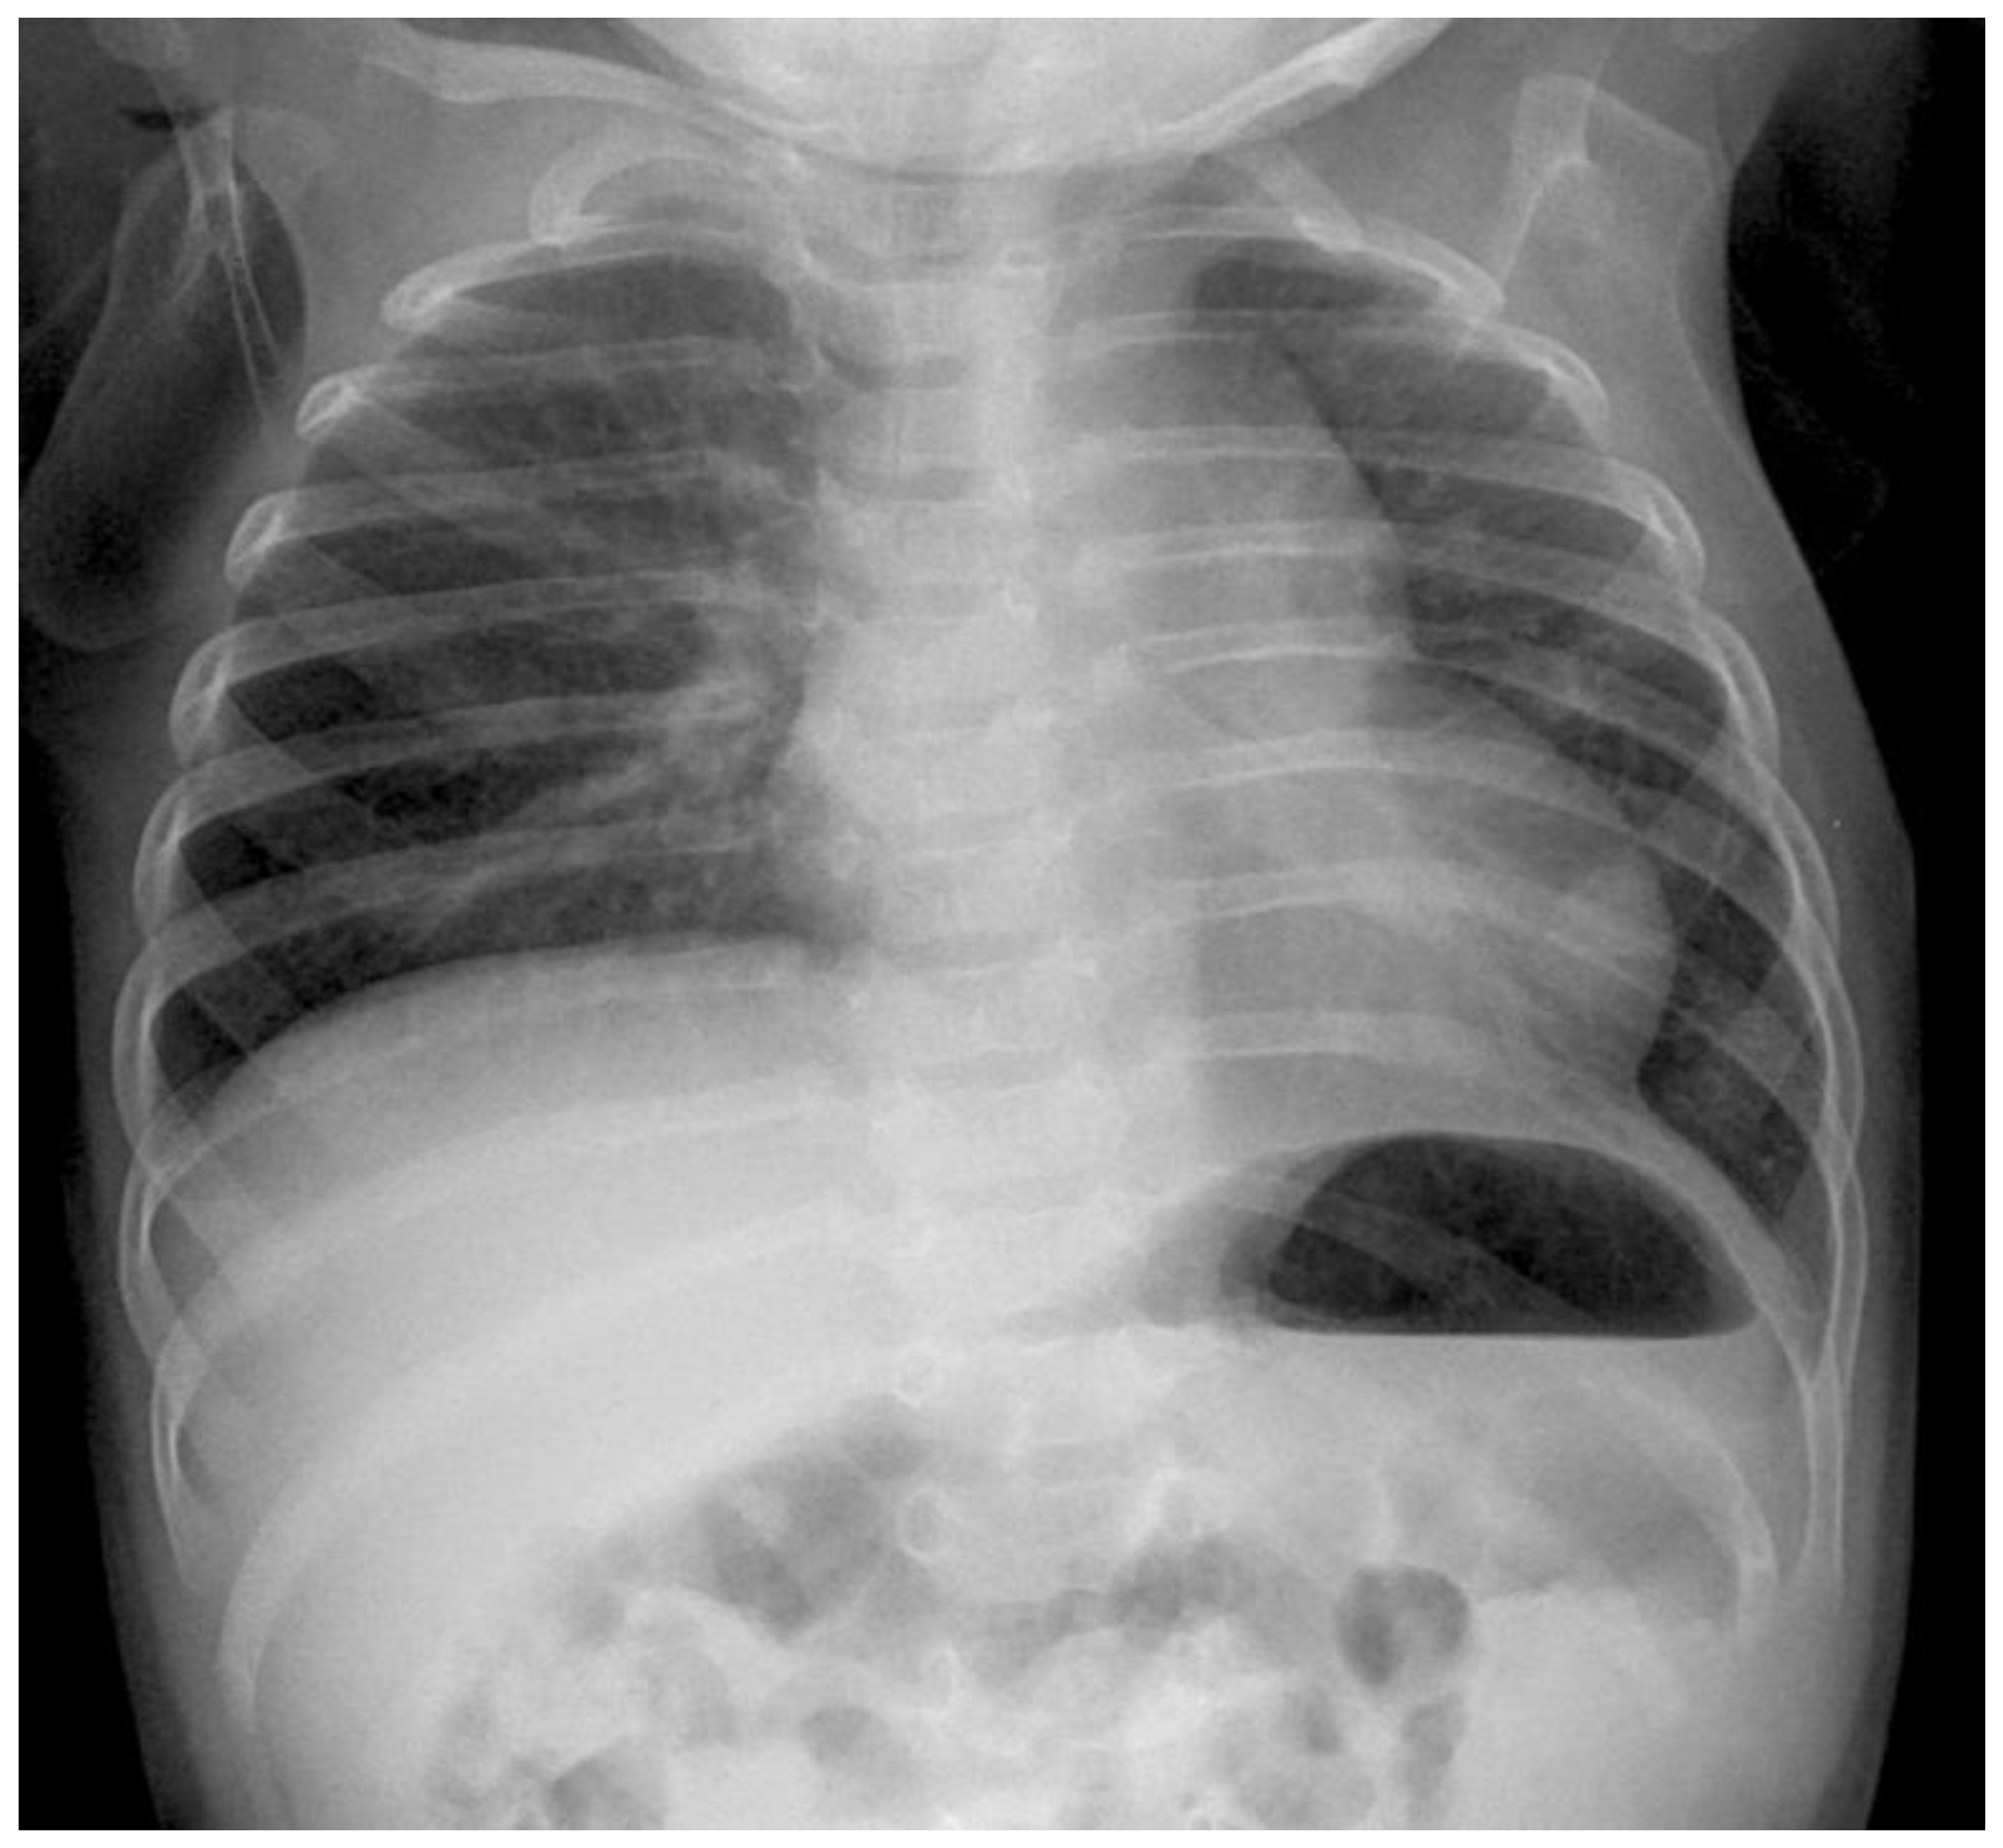

Postoperative follow-up: All patients left our operation room intubated and in cardiorespiratory stable condition. The mean ventilation time after operation including weaning was 75.8 h (range 25.5–132 h). The mean length of hospital stay was 19 days (range of 7–33 days). Postoperative clinical follow-ups were performed 2 and 6 months after hospital discharge with plane X-ray images (see Figure 7). Further follow-up examinations were performed every six months up to two years of age, thereupon, they were performed every year. Today, the mean follow-up time is 3.5 (1.1–6.3) years but in the future, the number will grow. Each patient was seen on average 5 (3–9) times after discharge and they remain in our follow-up schedule. The outcome of all seven patients to date was excellent, we had no recurrent hernias, no scoliosis, and no cases of intercostal neuropathy.

Figure 7. Radiograph of the same patient after 6 months.